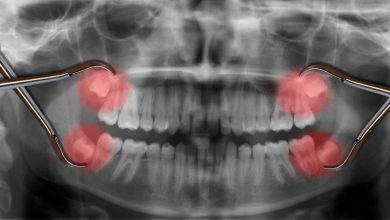

با دندان عقل چه کنیم؟

هر انسان بالغ، 32 دندان دارد که 4 عدد از آنها در انتهای قوس های دندانی می رویند. تاج این دندان ها در نوجوانی و…